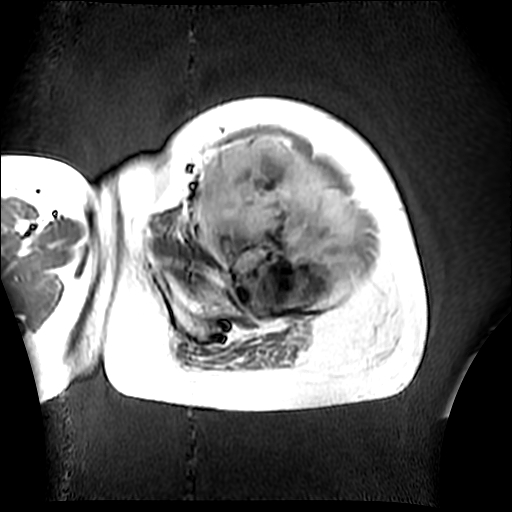

左侧大腿外伤10余年,当时情况不清,发现左侧大腿肿胀7年余,而后又有多次外伤史,近1年来出现疼痛,减重半年。查体:左侧大腿肿胀明显,皮温、肤色正常。

增强

软组织肿块,股骨破坏,增强不均匀强化-----支持恶性肿瘤